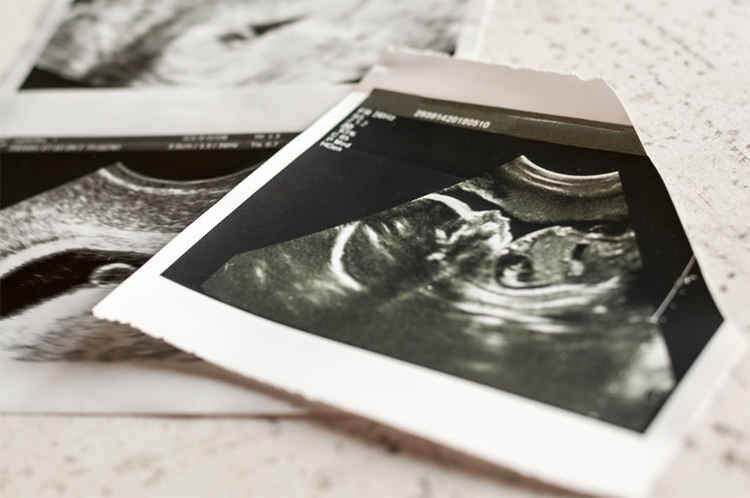

مبلغ نجومی سقط جنین غیرقانونی در ایران!

خبرگزاری دانشجو: طبق گفته یک ماما که سقط غیر قانونی انجام میدهد، اگر همه چیز نرمال باشد برای سقط جنین زیر سه ماه تقریبا ۷۰ میلیون و بالای ۴ ماه آن هم تنها یک هفته بیشتر از ۴ ماه با مبلغ ۱۵۰ میلیون کار را انجام میدهد.

یک پزشک عمومی در مورد هزینه این عملها میگوید که هزینه سقط جنین غیرقانونی تا ۴ ماه ۱۲۰ میلیون تومان است. البته افرادی هم هستند که چنین پولی ندارند، اما به این خاطر که ممکن است جانشان به خطر بیافتد با هزینه کمتر هم حاضر به انجام کار میشوم. اما اگر افرادی با تمکن مالی بالا برای این کار مراجعه کنند، بیش از ۱۲۰ میلیون از آنها میگیرم.